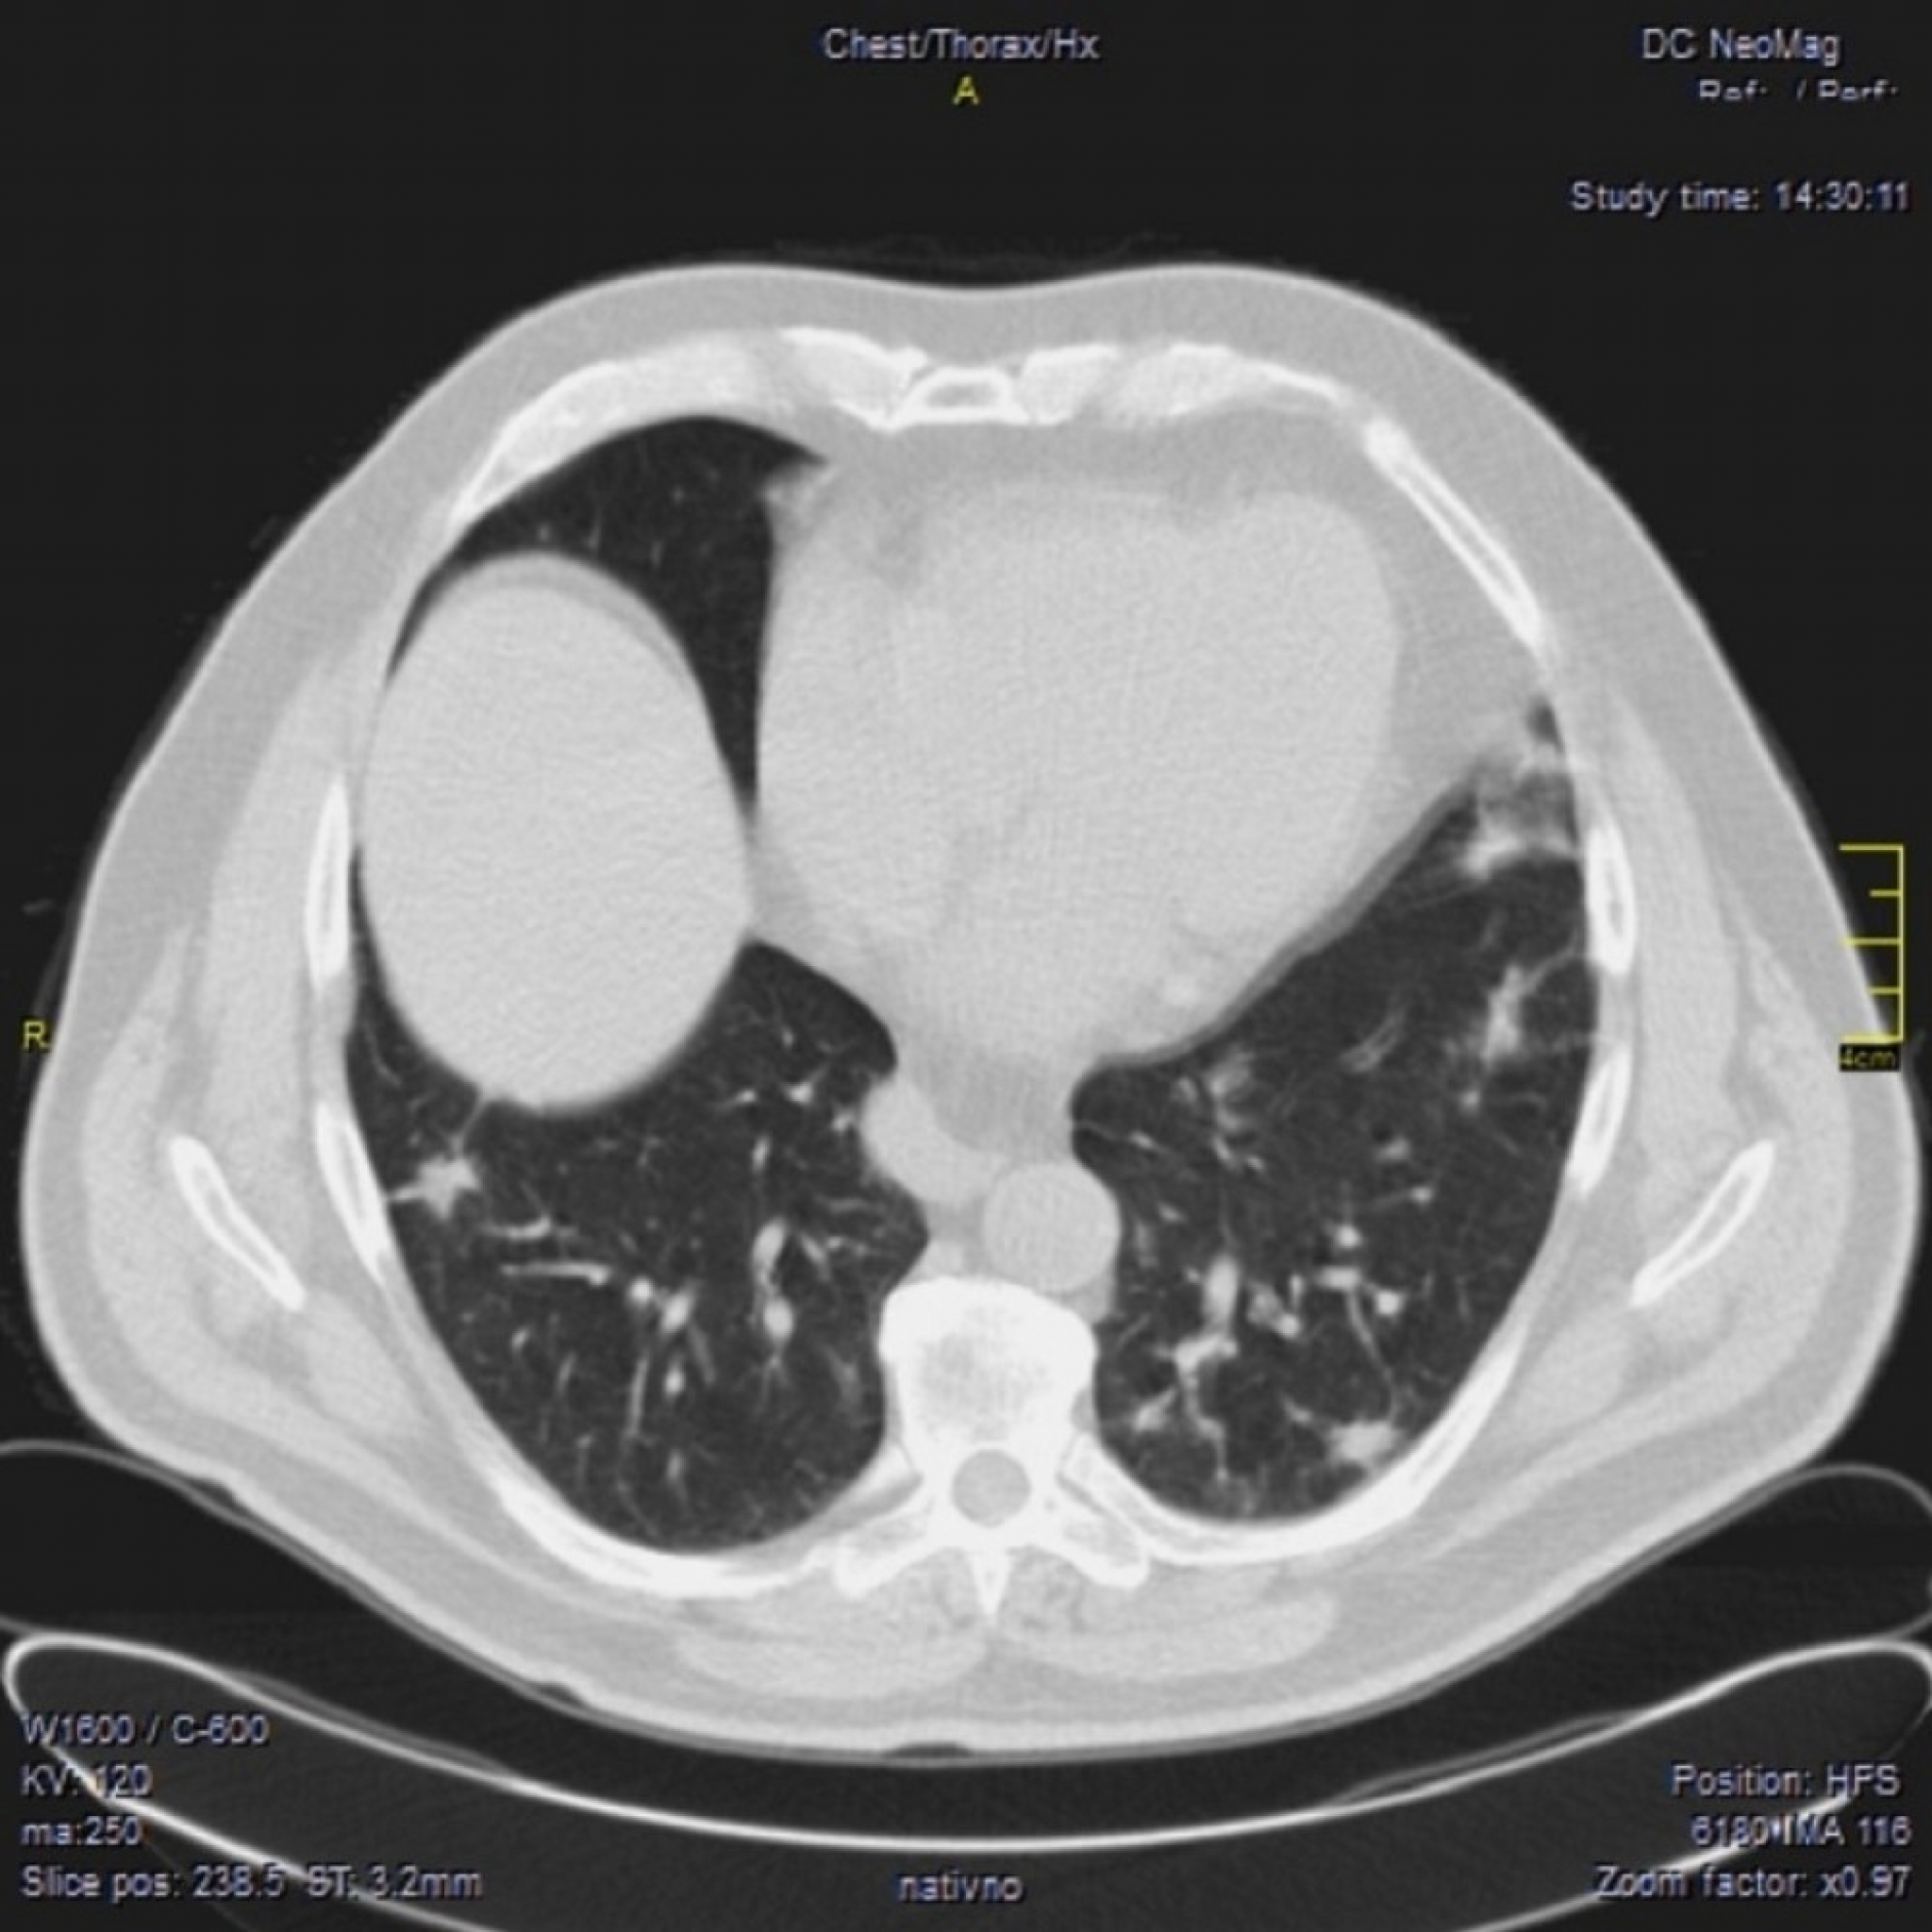

April 2021. Počinju da dolaze pacijenti koji imaju drugačiji nalaz.

Ono što je karakteristično je to da su ovo nalazi koji su 2. i 3. dana bolesti u I fazi.

Znači ne u progresivnoj, već u uvodnoj fazi kada uglavnom nema CT znaka. Fibrozne trake već drugog dana? Ground glass oko većih grana bronha. Kao da bolest ne može da sačeka, kao da klija gde stigne.

Klinička slika se razlikuje od britanskog soja. To se slažu i moji pulmolozi. Za sada je desetak pacijenata (kod mene), malo za zaključke, ali to su pacijenti u kratkom vremenskom periodu od 31.03.2021. godine do 14.04.2021. godine.

Neće mi biti iznenađenje ako se pokaže da već imamo novi soj virusa. Ne mogu da tvrdim da je brazilski, ali se svakako razlikuje.